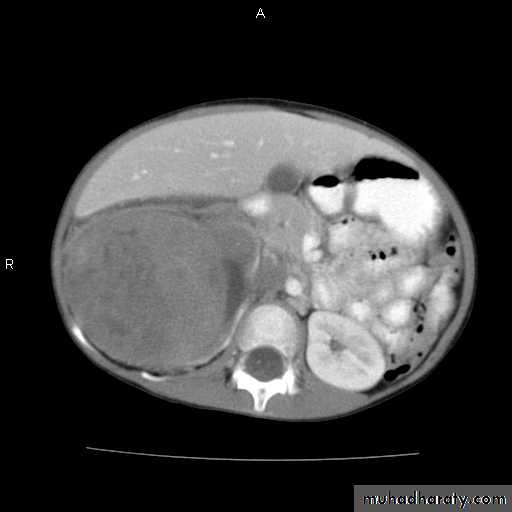

Wilms tumor: Signs and Symptoms

Abdominal mass

Often asymptomatic

Encapsulated

Mass enlarges toward pelvisAssociated anomalies, syndromes – 15%

WAGR syndromeWilms, aniridia, ambiguous genitalia, mental retardation

due to 11p13 deletion (WT-1)